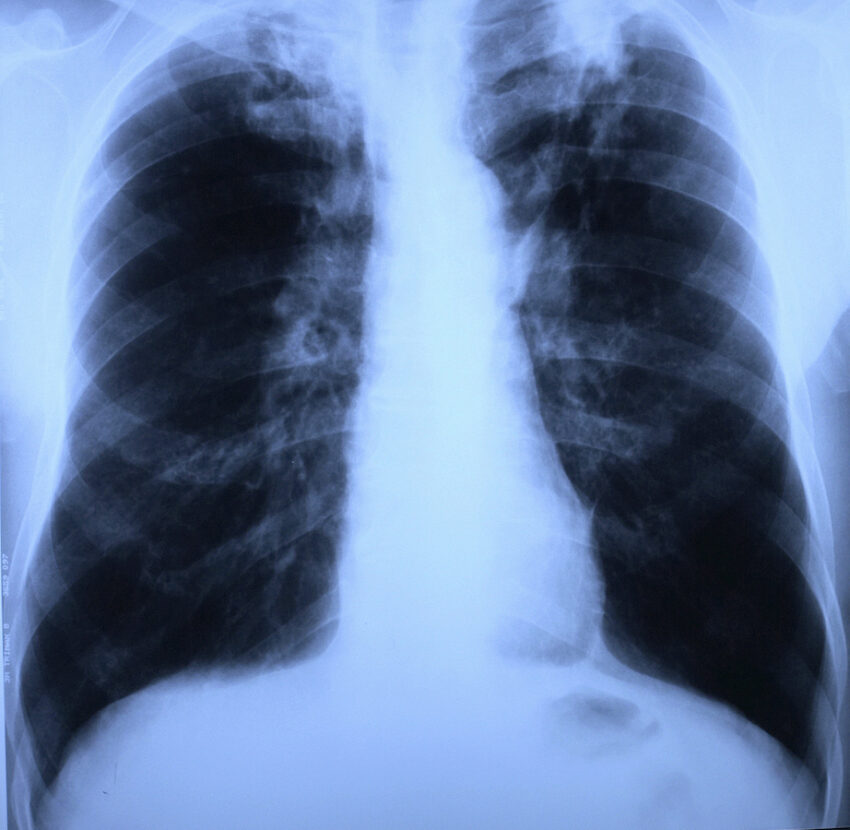

X-ray of lungs and thorax with upper lobes – tuberculosis on both sides.

Credit: Ernst-Georg Kohout